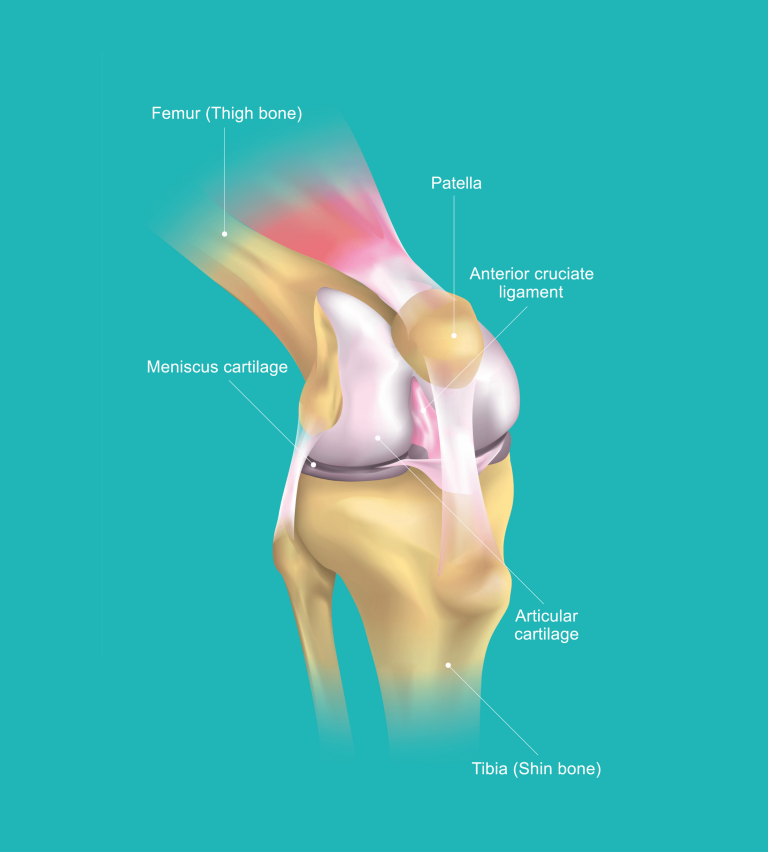

Before that, you should know a little bit about the anatomy and inner workings of the knee joint in order to understand the different injuries that may occur. The bones at the knee joint consist of the femur (thigh bone), the tibia (shin bone), and the patella (kneecap). The ligaments, which are fibrous connective tissue connecting the bones, help provide joint stabilisation.

Here’s a quick guide to help visualise the bones which make up your knee:

- The femur: runs from your thigh to your knee

- The tibia: runs from your knee to your ankle

- The patella: the triangular-shaped bone in front of the knee